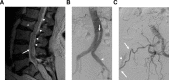

Sacral dural arteriovenous fistulas (SDAVFs) are rare, constituting no more than 10% of all spinal dural fistulas. They are most commonly fed by the lateral sacral artery (LSA), a branch of the internal iliac artery (IIA). Catheterization of this vessel requires either a crossover at the aortic bifurcation in cases of right femoral access or retrograde catheterization from the ipsilateral common femoral artery. We present the case of a 79-year-old man with tethered cord syndrome and a symptomatic SDAVF fed by two feeders from the left LSA. Spinal diagnostic angiography was made exceptionally challenging by an aorto-bi-iliac endograft, and selective catheterization of the left IIA was not possible. The patient could not undergo surgery due to multiple comorbidities, therefore embolization was considered the best approach. The procedure was carried out through a transradial access (TRA) with Onyx and n-butyl cyanoacrylate. The SDAVF was successfully treated and the patient made a full neurological recovery.